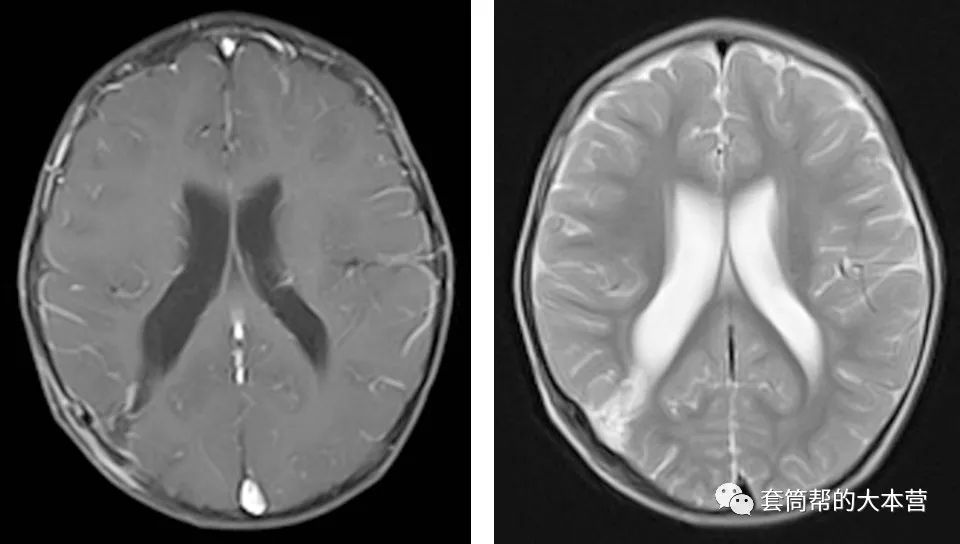

术后一个月,小宝宝回院复查。头颅磁共振证实了肿瘤全切除,而且手术的通道回弹很好,已经变得很窄,没有发生常规开颅手术时常见的脑穿通畸形。

术后一个月复查,手术通道很窄,无脑穿通畸形